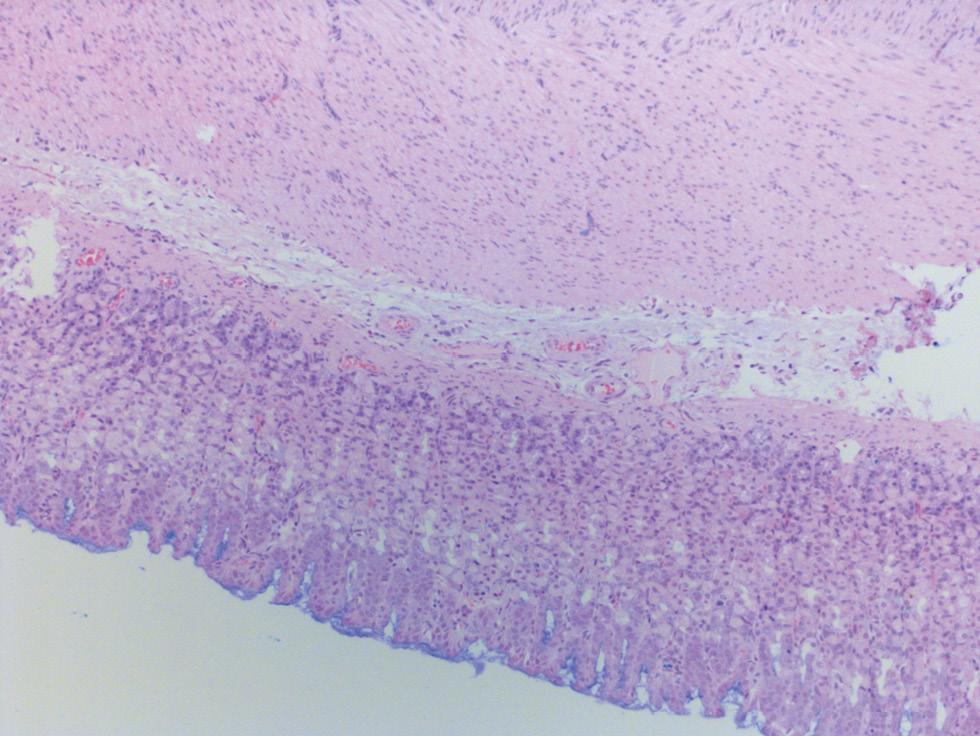

In the morphological study of the GMM in the atrophic gastritis rat model, we observed high villi, shallow pits and cervical regions, a uniform distribution of glands in the mucous membrane of the stomach body and antrum, weak lymphohistiocytic infiltration, eosinophil infiltration, and the presence of single plasma cells. Similarly, the muscular layer is represented by bundles of smooth muscle fibers, while the serous membrane is covered with a single layer of mesothelium. The thickness of the mucous membrane of the body of the stomach was 0.53 ± 0.04 mm, while that of the antrum was 0.21 ± 0.01 mm. Although that was less than in the control group, the difference did not reach statistical significance. During histochemical detection of glycosaminoglycans using Alcian blue stain at pH 2.5 in the stomach body, we observed that production did not increase, was diffused, and moderately expressed in the superficial parts of the GMM (Fig. 3). On the other hand, the production of glycosaminoglycans in the antrum of the stomach increased compared with that in the group of intact rats and was moderate both in the superficial parts and in the bottom parts of the glands (Fig. 4).

Fig. 3. Rat with atrophic gastritis modeling. Gastric body mucosa with enhanced glycosaminoglycans production in superficial epithelium / Рис. 3. Крыса с моделированием атрофического гастрита. Слизистая оболочка тела желудка с увеличением продукции гликозаминогликанов в поверхностном отделе эпителия

1 In the pictures 1–4 histology slides stained with hematoxylin and eosin with alcian blue additional staining, ×200 magnification.